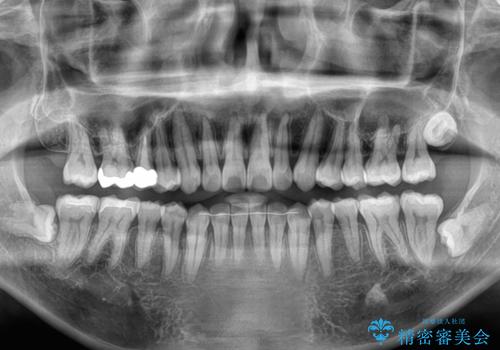

マウスピース矯正は、ワイヤー矯正と違い、とにかく自己管理が非常に重要となります。

毎日の装着時間をしっかりと守ってくださり、1年強の短期間で、あっという間に治療を終えることができました。